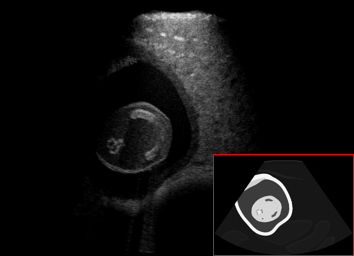

US simulation. We used a ray-tracing framework to render B-mode images from a geometric fetal model, by simulating a convex probe placed at multiple locations and orientations on the abdominal surface, with imaging settings listed in Tab 1. At each location, simply rasterizing a cross-section through the triangulated anatomical surfaces at the ultrasound center imaging plane provided corresponding semantic maps. Fig. 3 shows example B-mode images with corresponding semantic maps. A total of simulated frames were resized to and randomly split into training-validation-test sets by 80-10-10%.

Discussion. Note that, despite both being fetal images, the simulated and the real images have substantially different anatomical contents, which makes the translation task extremely challenging. Nevertheless, our proposed framework is able to generate images with appearance strikingly close to real images, with far superior realism than its competitors. Besides sim-to-real translation, given its multi-domain conditional nature, our proposed framework without any further training can also translate images between the other domains, e.g. seg-to-real or seg-to-sim, with examples presented in Fig. 5.